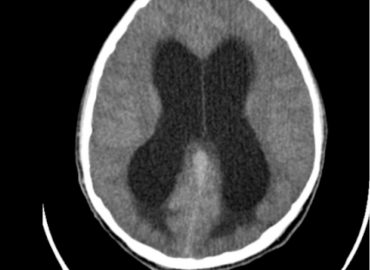

MASCULINO 19 AÑOS APP: NIEGA. ATX: NIEGA. AHF: NIEGA MH: NIEGA MC: CEFALEA, CONVULSIONES